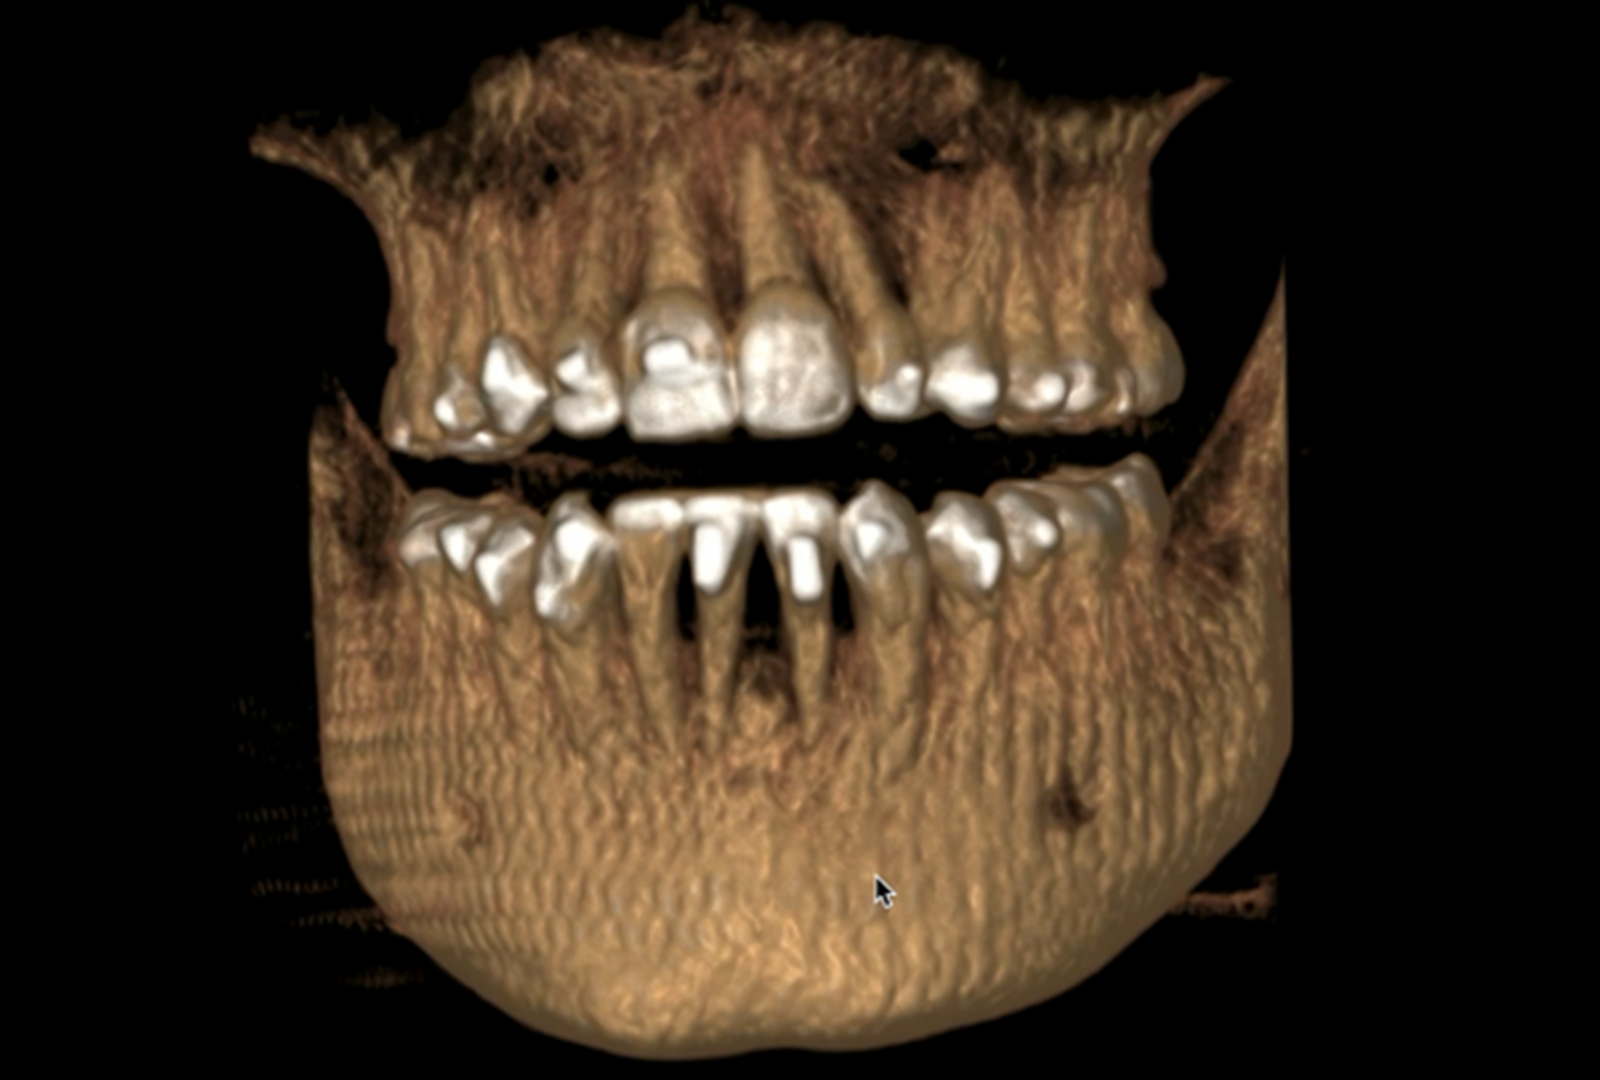

Deze twee cursussen op geavanceerd niveau zijn ontworpen om clinici vertrouwd te maken met de concepten en vaardigheden voor het diagnosticeren en het behandelplan voor zelfs de meest uitdagende casussen. Deelnemers leren hoe ze uitgebreide behandelplannen voor multidisciplinaire casussen kunnen benaderen, organiseren en uitvoeren. Aan het einde van de cursus zullen clinici zelfverzekerd zijn in het behandelen van complexere gevallen en in staat zijn om hulpmiddelen en hulpstoffen die de controle over de wortel- en lichamelijke bewegingen verbeteren, naadloos te implementeren. Aan het einde van deze serie hebben deelnemers een verhoogde expertise in CAT opgebouwd. CAT is een populaire keuze geworden voor patiënten die op zoek zijn naar een minder ingrijpende orthodontische optie, waardoor hun zorgstandaard wordt verbeterd, evenals de beleving van elke patiënt die hun praktijk bezoekt.

- Begrijpen hoe de etiologie van complexe casustypes helpt bij het definiëren van de mogelijke behandelopties

- Behandeling van open beten, klasse II en klasse III malocclusies

In deze cursus worden clinici begeleid door een branche deskundige door een reeks complexe casustypen om de beste werkwijzen te leren voor het plannen van de behandeling van dit soort casussen. Artsen leren hoe ze aligners kunnen combineren met de juiste hulpmiddelen als een doeltreffend middel om complexe orthodontische problemen aan te pakken.

Deze cursus is ontworpen om artsen op een gevorderd niveau bij aligner behandelervaring te helpen bij het plannen van de behandeling voor complexe, multidisciplinaire casussen. Artsen leren om de behandeling met succes en strategisch te plannen en hoe ze clear aligner-therapie kunnen integreren in andere vormen van patiëntenzorg. Restauratieve en prosthodontische behandelingen in combinatie met aligner-behandeling worden besproken, aangevuld met tips over de volgorde en overlap van zorgfasen om de behandeltijd te minimaliseren. Deze interactieve cursus volgt een casusgebaseerde benadering waarbij artsen de gelegenheid krijgen om meer te weten te komen over de behandelresultaten van de arts die de casus behandelde.